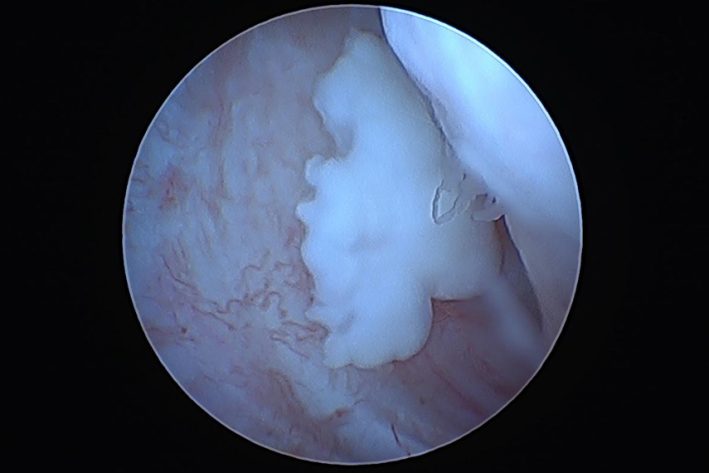

freie Schuppe